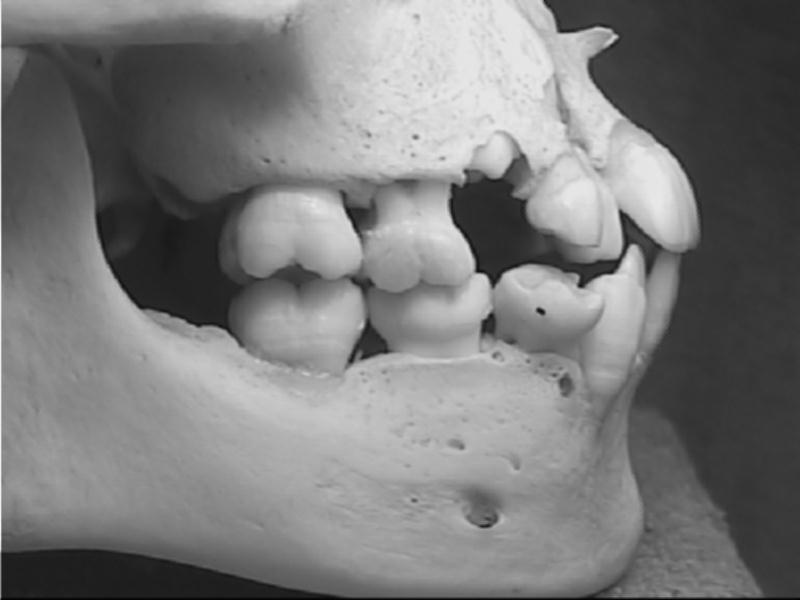

Sơ đồ mầm răng sữa trẻ sơ sinh trên xương hàm |

Xương sọ vùng hàm trên và dưới trẻ sơ sinh |